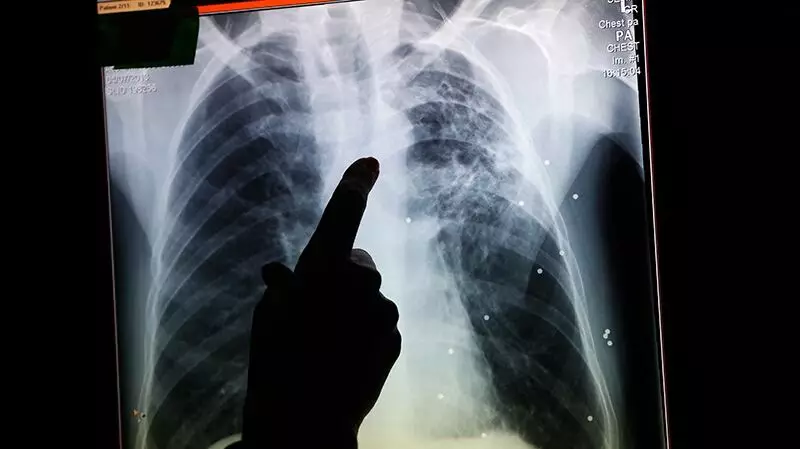

Health authorities in Edmonton have officially declared a tuberculosis outbreak among the city's homeless population, raising significant concerns about public health and community safety. The declaration came on November 13, 2025, marking a serious development in the ongoing challenges facing Edmonton's most vulnerable residents.

Tuberculosis, commonly known as TB, is a serious infectious disease that primarily affects the lungs. The bacteria spreads through the air when infected people cough, sneeze, or spit. What makes this outbreak particularly concerning is its occurrence within the homeless population, where crowded living conditions in shelters and limited access to healthcare create ideal conditions for the disease to spread rapidly.

The outbreak declaration follows increasing cases detected among homeless individuals across multiple shelters and support facilities throughout Edmonton. Public health officials are working diligently to contain the spread while ensuring those affected receive proper medical treatment.